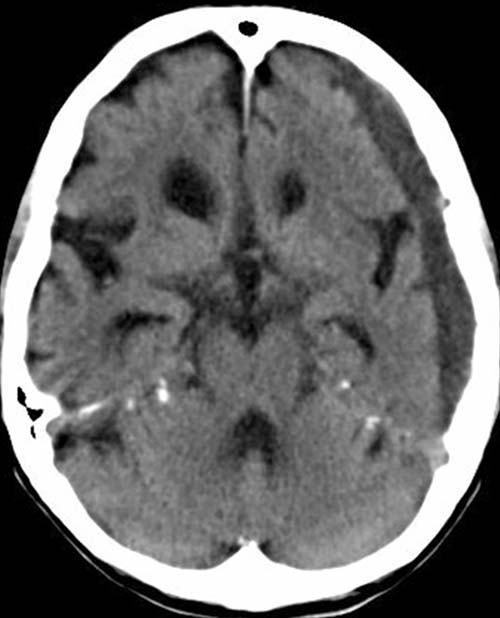

CCT nativ (d.h. ohne Kontrastmittel)

Zwischen Kalotte und Hirnoberfläche sichelförmige hypodense (20-40HE) Raumforderung links.

Deutlich erweiterte

innere und äußere Liquorräume außerhalb der sichelförmigen

Raumforderung.

Chronisches

Subduralhämatom (SDH) links

Nebenbefundlich: Hirnatrophie.